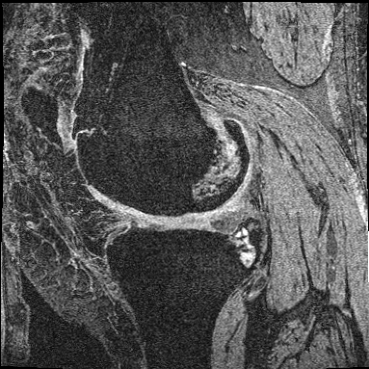

Inverse consistent rigid, affine, nonparametric, and MLP registration. We train networks on MNIST 5s using the methods in Secs. 3 and 4, demonstrating that the resulting networks are inverse-consistent. Our TwoStepConsistent (TSC) operator can be used on any combination of the networks defined in Sec. 3. For demonstrations, we join an MLP registration network to a vector field registration network, and join two affine networks to two vector field networks. Fig. 2 shows successful inverse-consistent sample registrations.

OAI Knee MRI We train and test on the split published with [22], with 2532 training examples and 301 test pairs from the Osteoarthritis Initiative (OAI) [16]444https://nda.nih.gov/oai. We evaluate using the mean Dice score of tibial and fibial cartilage. To compare directly to [22, 7, 23] we train and evaluate at [80x192x192].

| Moving Image | Warped Image | Fixed Image | Moving Image | Warped Image | Fixed Image |